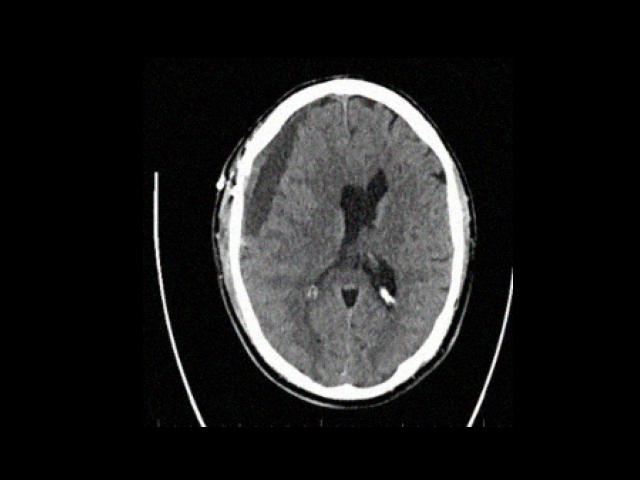

Sample Gallery